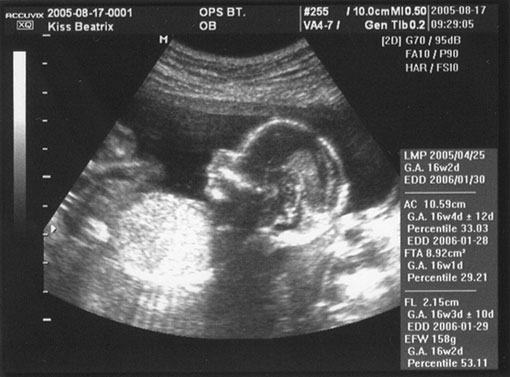

16. hét